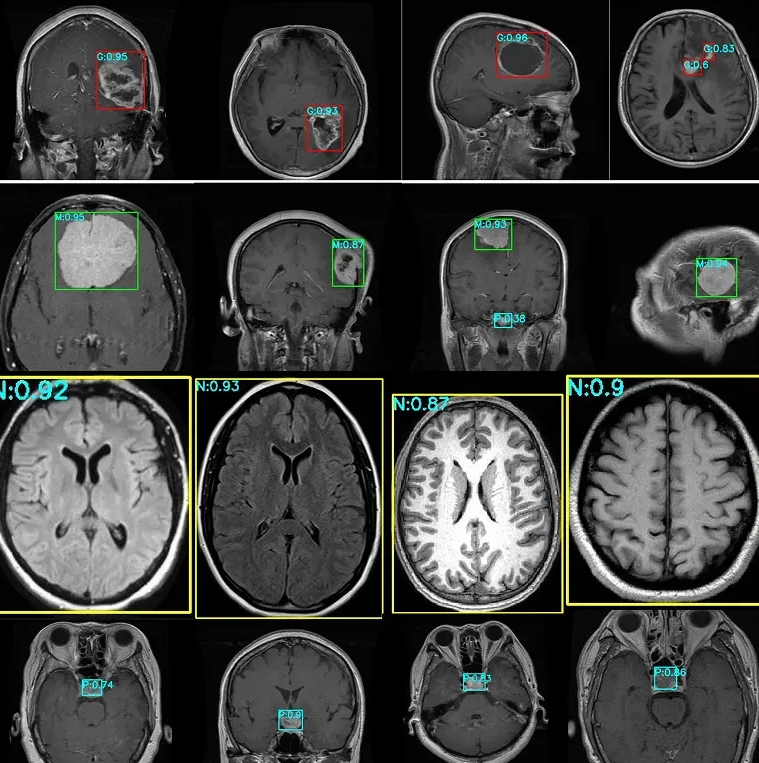

医生们常常花费大量时间查看医学影像,以确保不会遗漏任何信息。如今,许多医院开始探索尖端的目标检测技术来帮助加快这一过程。这反映了医疗保健领域的一个更广泛趋势:视觉AI正越来越多地用于支持早期检测、快速诊断和更一致的影像分析。

目标检测可用于快速突显可能需要关注的区域,从而辅助决策并改善患者治疗效果。例如,像YOLO11这样的模型可以帮助医生在MRI扫描中发现脑肿瘤。

由于YOLO11能够识别MRI扫描中的细微模式,它可以帮助更准确地发现小型或早期肿瘤。虽然医生做出最终诊断,但像YOLO11这样的工具可以通过更早地提示潜在问题来帮助简化他们的审阅工作,确保重要的信息不被遗漏。